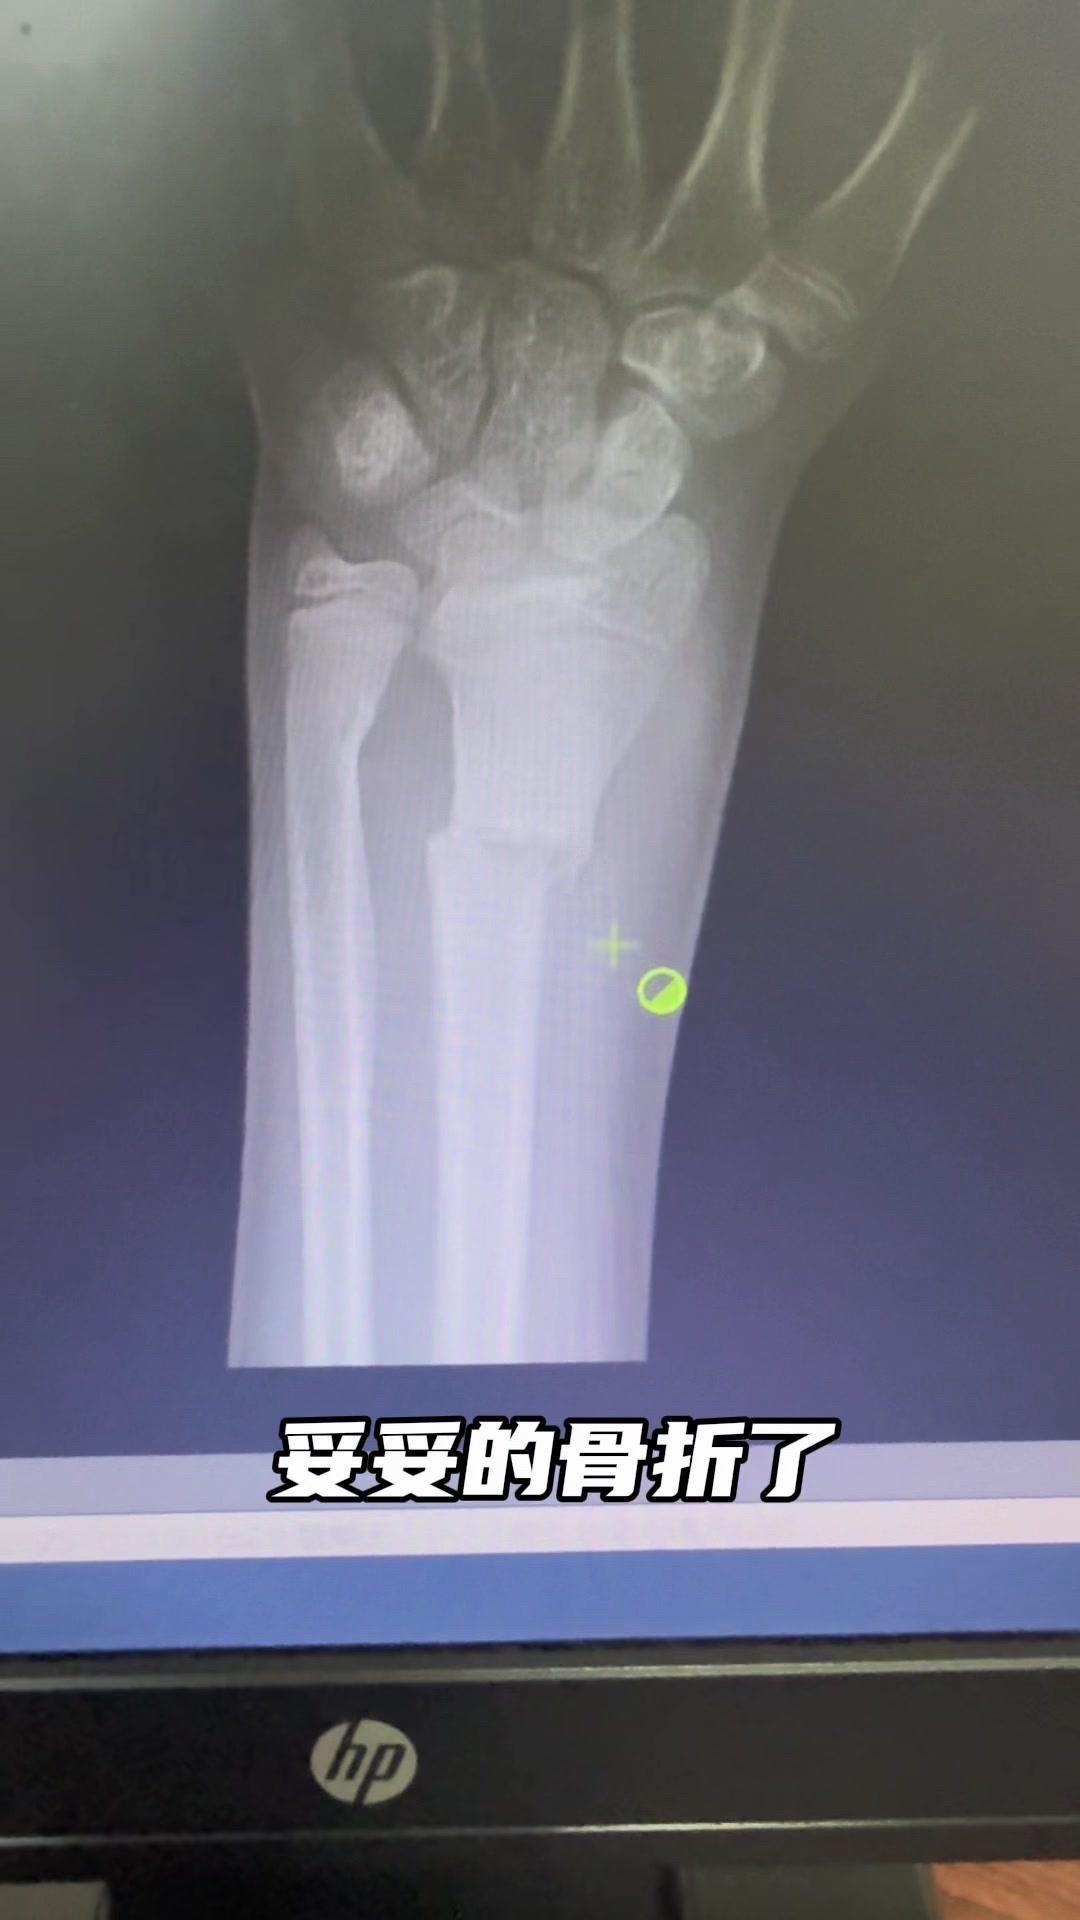

儿童骨折别拖延!💡上周接诊一个10岁女孩,摔了一跤后腕部疼痛还伴有畸形,家长觉得是小伤没在意,结果一周后孩子疼得更厉害,畸形也更明显了。来医院拍片一看,妥妥的骨折,而且才一周就开始出现模糊骨痂,掌区还有45度左右的成角畸形。家长这才意识到问题严重性,其实孩子受伤后出现疼痛、畸形,哪怕看起来不严重,也得及时检查,别让小问题拖成大麻烦。